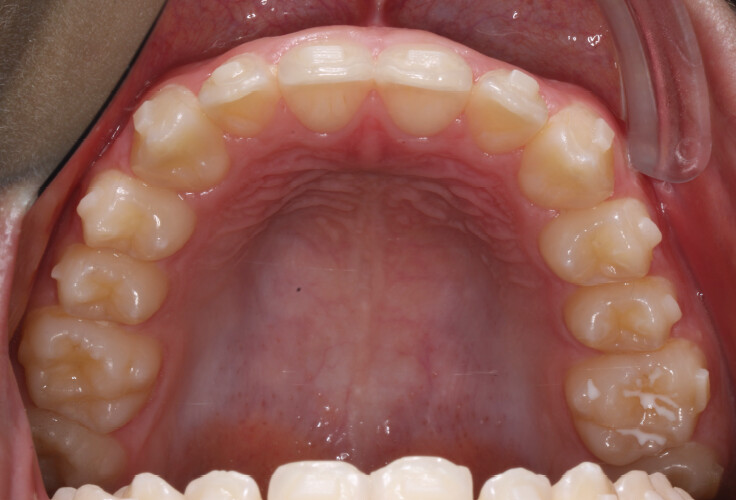

A 13-year-old male patient presented with a deep bite, characterized by near-complete coverage of the mandibular incisors. Clinical evaluation revealed bi-arch crowding, dental rotations, and proclination of the maxillary lateral incisors, contributing to the patient’s esthetic concerns. The facial profile was retrusive, consistent with mandibular retrognathism, and no significant periodontal abnormalities were detected.

• Arch expansion to resolve crowding and improve transverse coordination;

• Programmed intrusion of the maxillary central incisors to reduce the gingival display and correct the gummy smile;